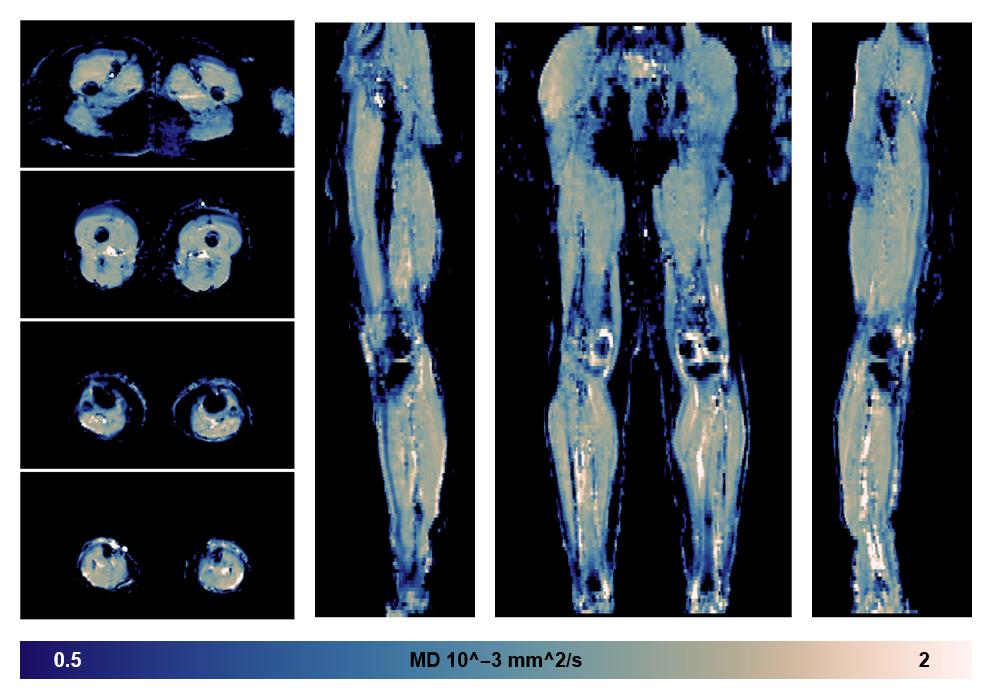

• Mean diffusivity

IVIM corrected whole leg muscle mean diffusivity obtained from diffusion tensor imaging.